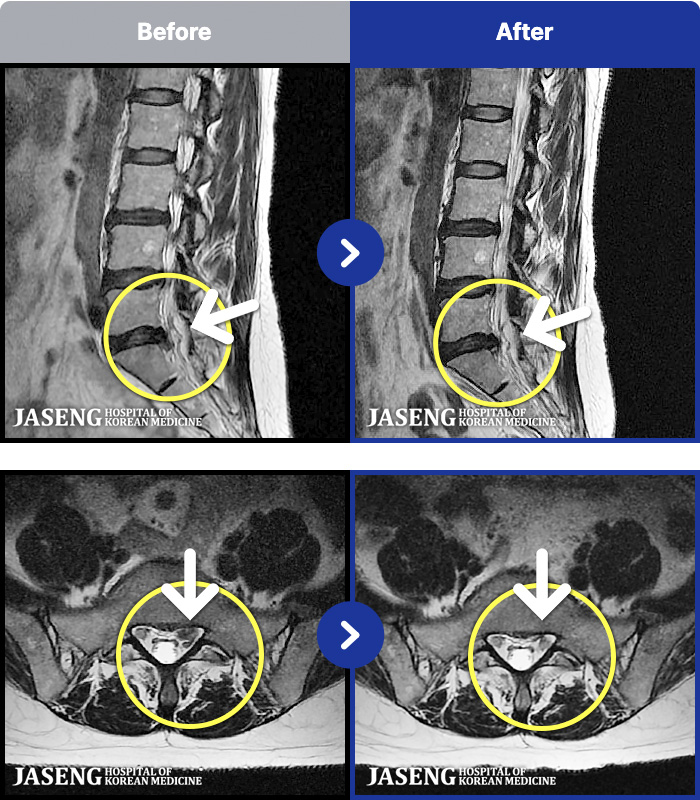

[Կñ:21.12.17~22.07.04]

[_㸮ũ] 㸮

No.53

ȸ 97

2026.01.09